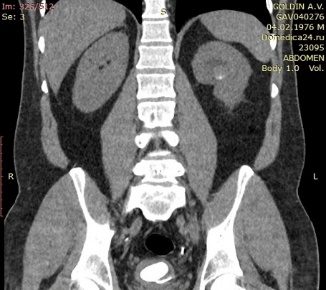

Краткая информация о пациенте Пациент Г., 45 лет. Считает себя больным в течение года, когда впервые был госпитализирован в городскую районную больницу с левосторонней почечной коликой. На момент обращения выявлен камень левого мочеточника, по поводу чего (10.08.2020 г.) выполнялась контактная уретеролитотрипсия слева, установка внутреннего мочеточникового стента. В последующем для удаления стента в стационар не обращался. С июня 2021 г., стал отмечать боль в поясничной области слева. Обследовался амбулаторно, по результатам компьютерной томографии диагностированы внутренний мочеточниковый стент слева, камень в мочевом пузыре на дистальном конце стента, размерами до 3,8 см и коралловидный камень в левой почке, размерами до 3,4 см. Госпитализирован в клинику урологии для оперативного лечения.

Компьютерная томография живота, таза (рис. 4, рис. 5).